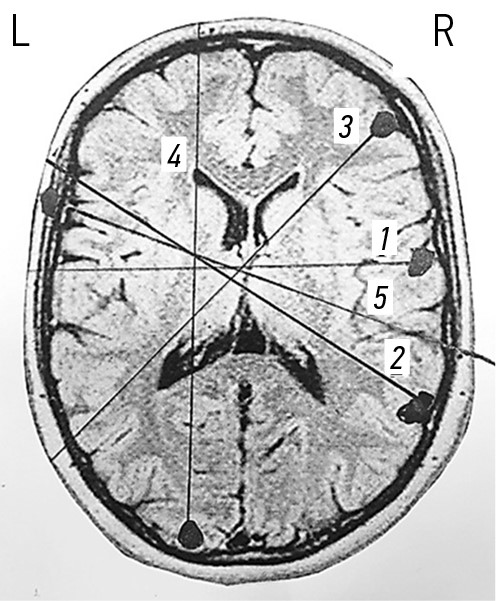

Ходы раневых каналов при огнестрельных проникающих осколочных ранениях черепа и ГМ, также примеры диагнозов продемонстрированы на рис. 3–7.

Рис. 3. Огнестрельные проникающие слепые простые и радиальные ранения черепа и головного мозга. Примеры диагнозов: 1 — минно-взрывное ранение (МВР). Огнестрельное осколочное слепое проникающее простое ранение правой лобной доли головного мозга; 2 — МВР. Огнестрельное осколочное слепое проникающее радиальное ранение правой лобной доли головного мозга; 3 — МВР. Огнестрельное осколочное слепое проникающее радиальное двуполушарное ранение левой теменной доли головного мозга.